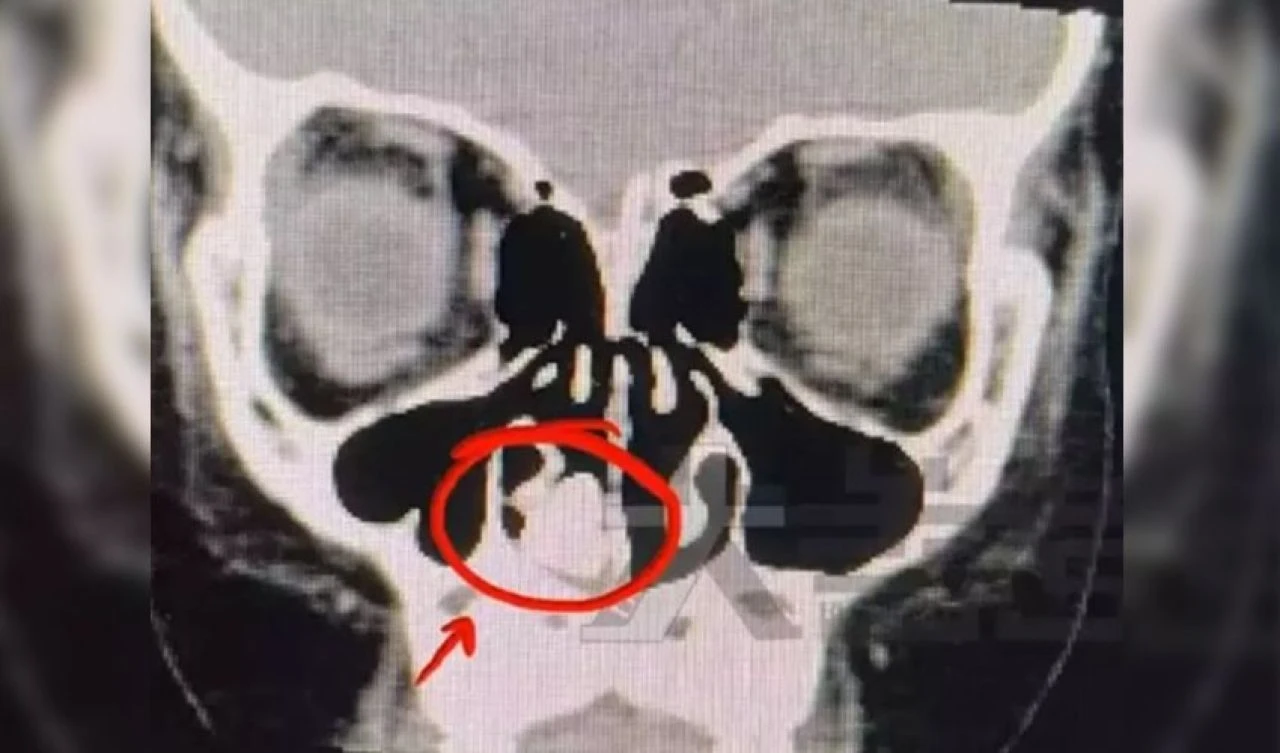

Yapılan detaylı inceleme ve röntgenler sonrası doktorlar çocuğun burun boşluğunda yabancı bir cisim olduğunu fark etti.

Yabancı cismin en az 2 yıldır çocuğun burun boşluğunda olduğu öğrenildi. Büyük miktarda yağ tabakasıyla kaplı olan cisim için doktorlar acil ameliyat ile duruma müdahale etti. Çocuğun burun boşluğundan başarılı bir ameliyat ile çıkarılan cismin paslanmış bir vida olduğu tespit edildi.